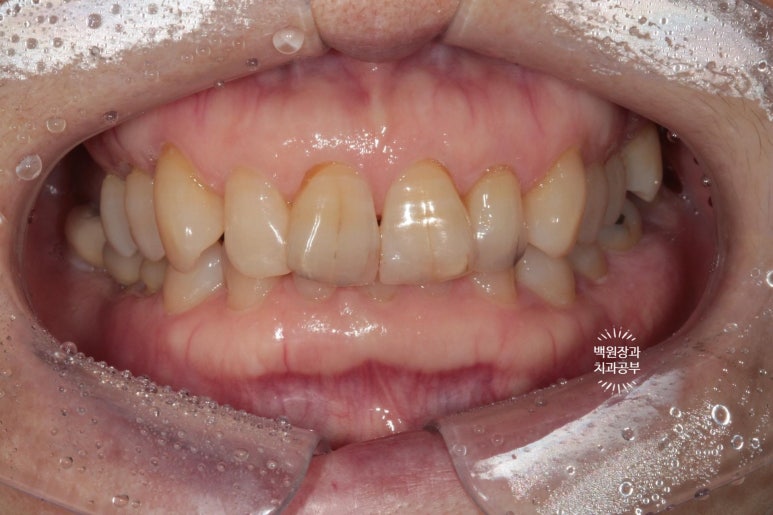

처음 내원하셨을 때 정면 사진입니다.

딱 봐도 위 대문니 두개에 큼지막한 세로 금이 관찰되네요. 환자분의 걱정 포인트이자, 콤플렉스였던 앞니 금.

생긴지 오래 되었을터인데, 시간이 흘러 착색까지 생겨버렸습니다. 50년 이상 사용한 치아에는 크랙이 많이 생길 수 있죠.